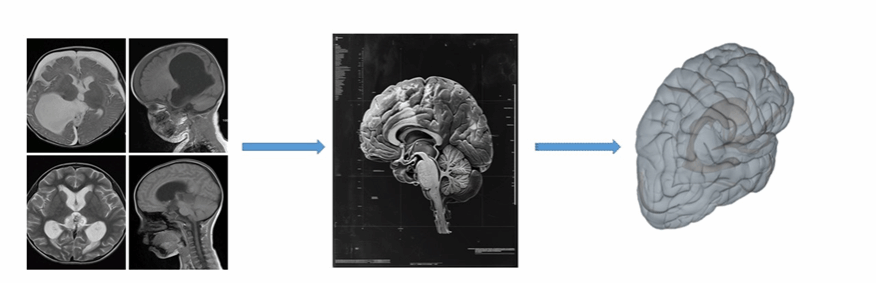

充分了解解剖位置和脑室穿刺的相对关系:在脑室引流中,一般根据患者病情选择穿刺点,因此,充分了解解剖相对位置就显得尤为重要,本系统通过解剖、影像、临床等多种方式各种角度详细的展示解剖知识,从而增加术者对本技术的了解。基于真实临床影像数据进行三维重新生成可交互可编辑的三维模型,结合计算机三维技术实现结构介绍及手术流程操作模拟。

图4 根据影像三维重新生成可交互的三维模型